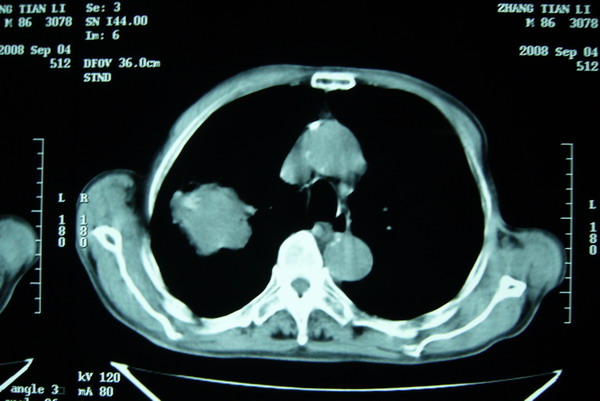

标题: CT15579:男 86岁 咳嗽 咳少量白痰 发热2天 吸烟史60年 [打印本页]

标题: CT15579:男 86岁 咳嗽 咳少量白痰 发热2天 吸烟史60年

右肺上叶巨大软组织肿块,轮廓不规则,纵隔内有肿大淋巴结,首先考虑肺癌。

右上肺一不规则团块,边缘有分叶和毛刺,纵隔有淋巴结肿大。右肺周围性肺癌首先考虑。